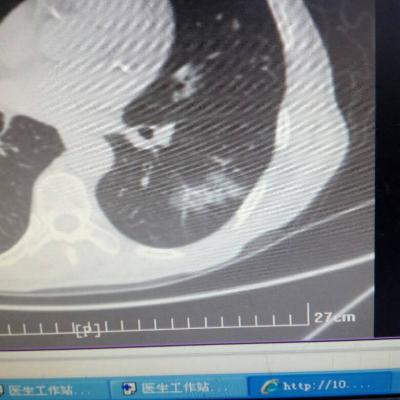

主诉:反酸、烧心5年,加重1年。 病史:患者5年前饮酒出现反酸烧心,并嗳气症状,剑突下烧灼感,饮酒及平卧后加重,无恶心呕吐,无腹痛腹泻,无吞咽困难,服用“达喜”后症状可缓解,易反复发作。3天前我科门诊示:胃镜反流性食管炎(LA-B),现为进一步诊治入院。

1.胃食管反流病 1.1反流性食管炎LA-B 2.食管裂孔疝 处理:患者诊断明确,行腹腔镜下食管裂孔疝修补术+胃底折叠术。

患者术后一周出院,反酸、烧心、嗳气症状明显缓解,无吞咽不畅等症状。 讨论:对于诊断有食管裂孔疝病人的胃食管反流病,且用药有一定疗效,建议行手术治疗,行腹腔镜下食管裂孔疝修补术,修补了膈裂孔,同时行胃底折叠术,加紧了贲门括约肌压力,共同形成抗“反流瓣”。